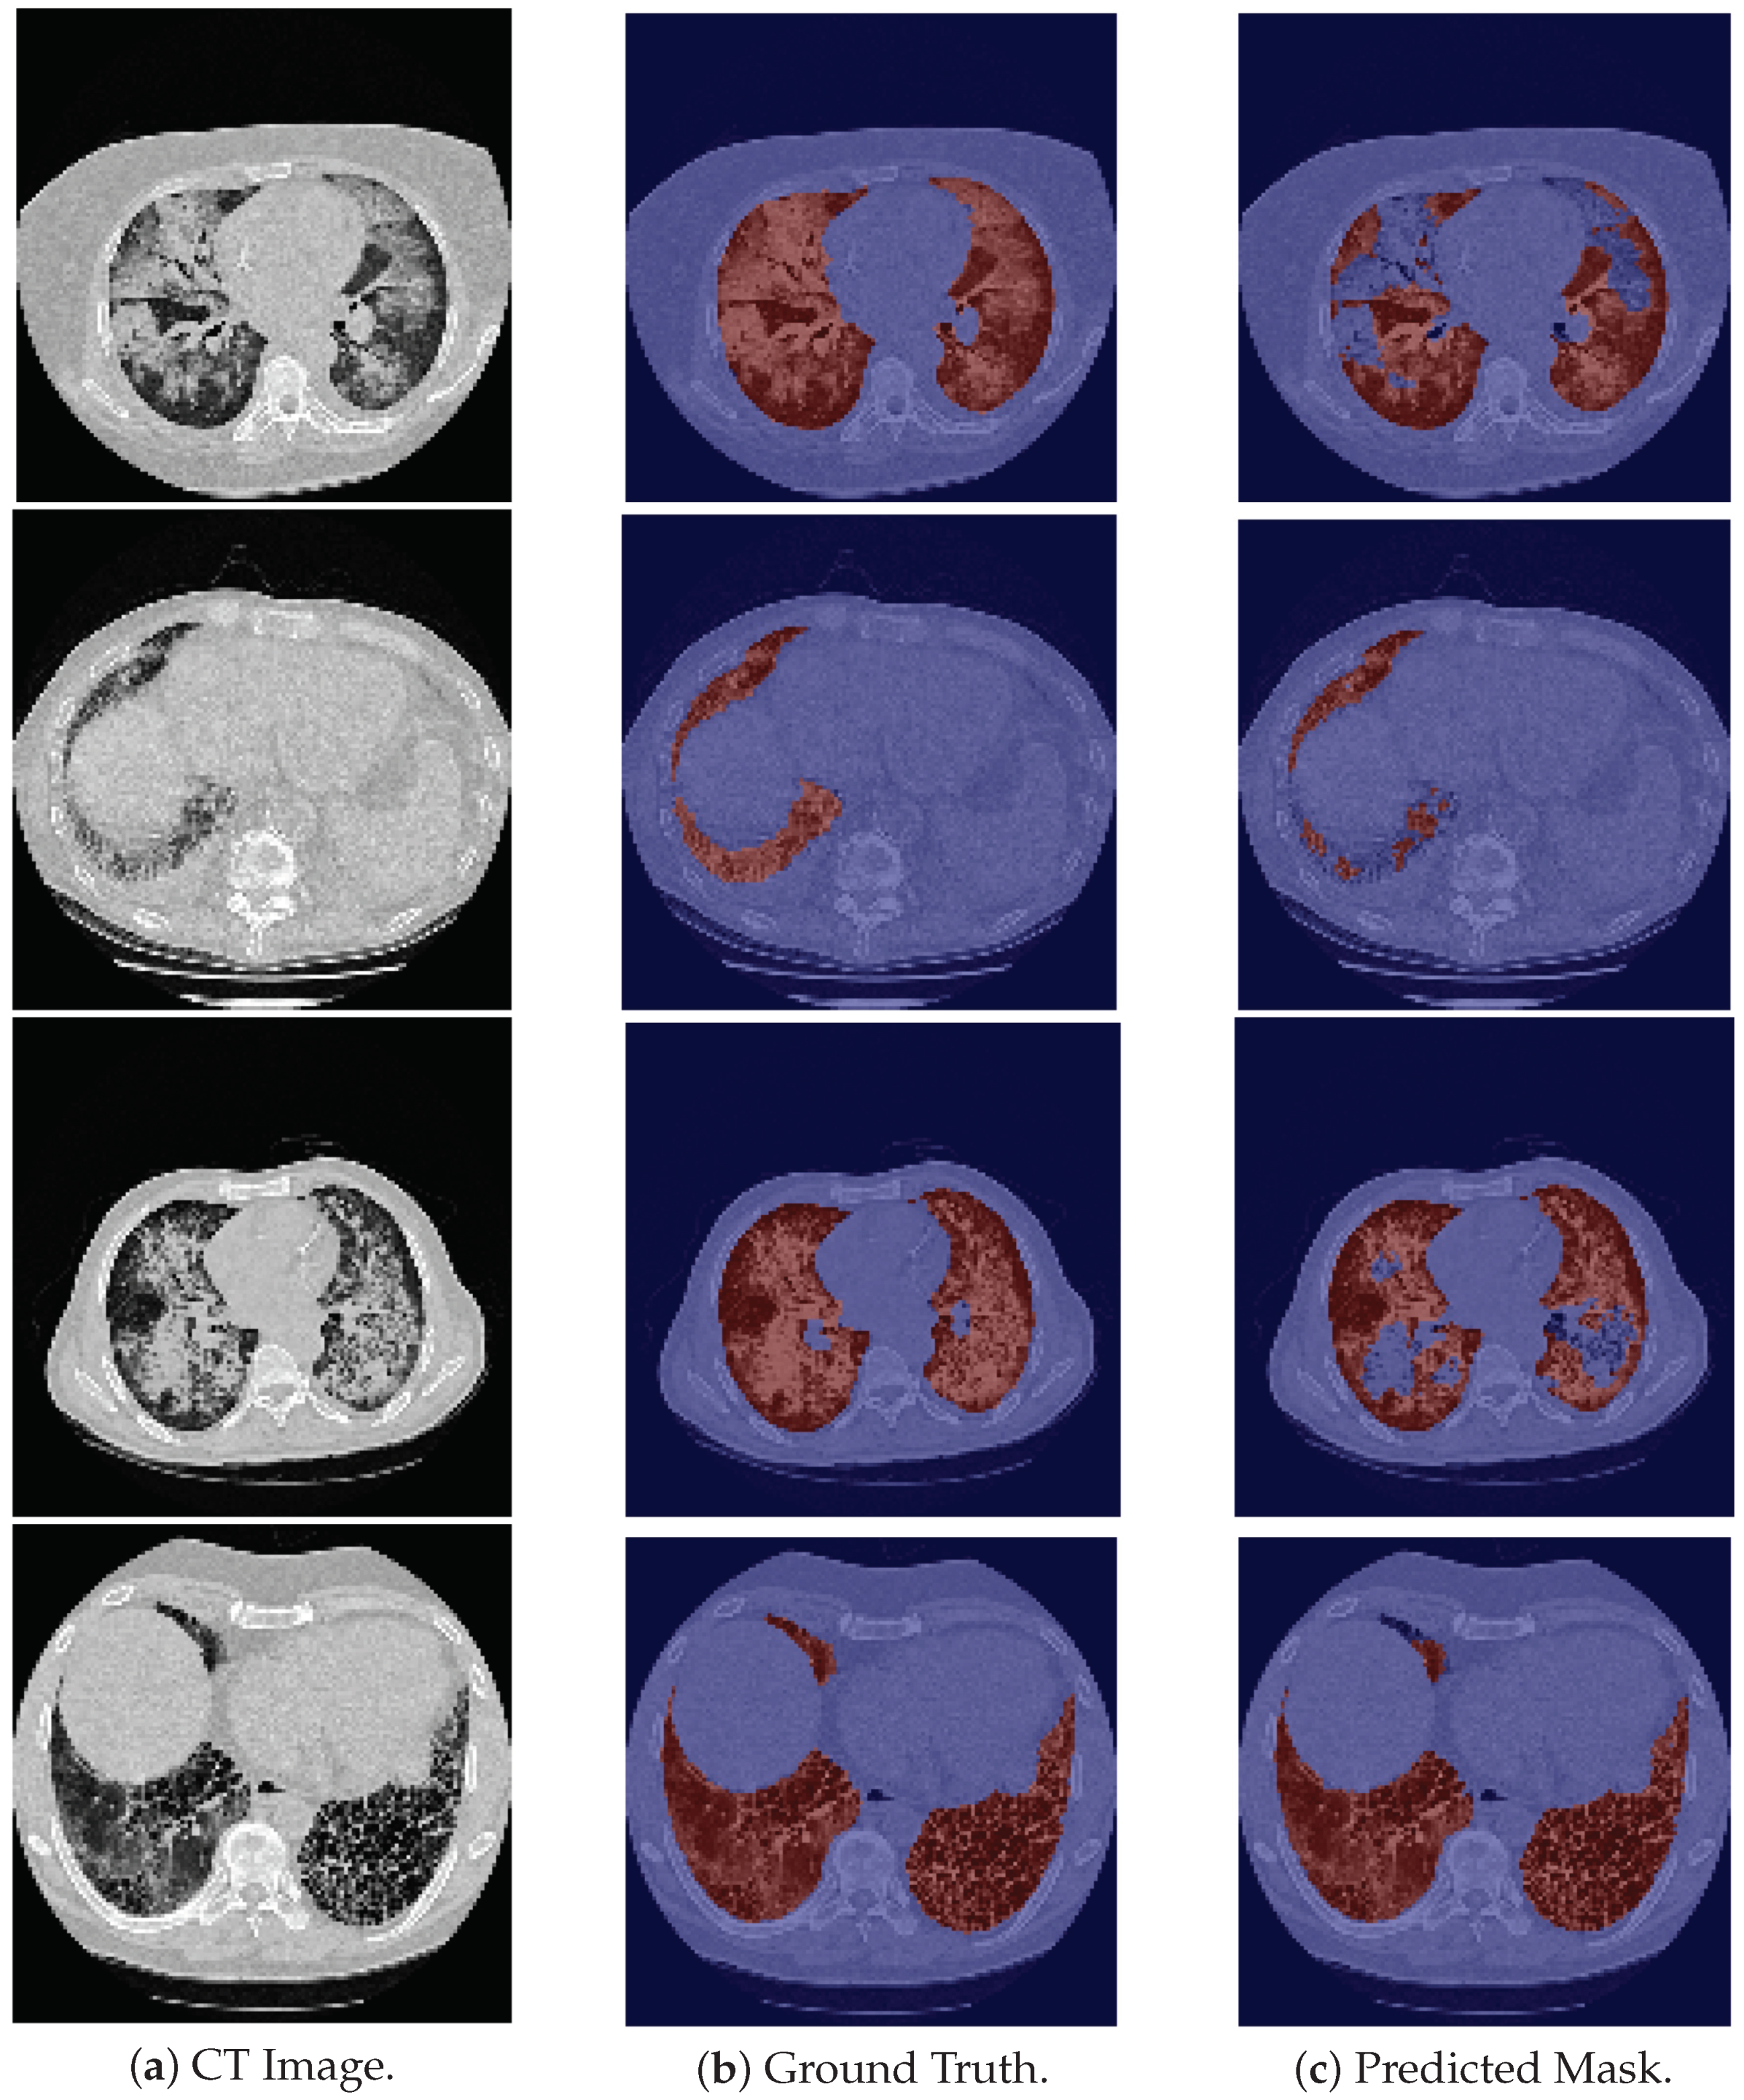

With respect to the 24-LCTSC dataset, the model is generally able to correctly segment the pulmonary images (see the first row in Figure 2), but fails to identify their initial slices, which correspond to the base of the lung, leading to a decrease in the DSC (see the second row in Figure 2). Furthermore, for one of the patients, the masks produced by the model seem to be more accurate than the ground truth images, as the latter excludes part of the lung parenchyma. An example is shown in the third row in Figure 2. Therefore, even though this contributes to a lower DSC due to the discrepancy between them, the predicted mask is more precise. On the other hand, there are cases in which nodules are not included in the ground truth, and there are elements that the model does not include as well, giving rise to a higher DSC, although incorrectly classified. An example is depicted in Figure 2, fourth row.

Figure 2. Examples of LCTSC images, the ground truth and the predicted mask. From top to bottom the examples are, respectively: good segmentation example; an example in which the model fails to segment the base of the lung; an example of a ground truth image that excludes part of the parenchyma of the lung; an example that excludes a nodule in its ground truth, and which is also misclassified by the model.

Another limitation comes from the annotations of the datasets. Those annotations come from different projects and followed different segmentation guidelines. There is no consensus on the inclusion/exclusion of some structures, such as airways or tumor masses. Examples of airways inclusion are shown in the second, third, fourth, and fifth rows in Figure 3 that belong to the HUG-ILD dataset, and examples of airways exclusion are shown in the last row in Figure 2, the first row in Figure 4, and the last row in Figure 5, that belong to the LCTSC, VESSEL12, and CHUSJ datasets, respectively. Examples of tumor masses inclusion are shown in last two rows in Figure 5 that belong to the CHUSJ dataset, and examples of exclusion are shown in the last row in Figure 2 that belong to the LCSTC dataset. Ideal, a very objective protocol of segmentation should be followed for the entire dataset annotation (training and test set) in order to not create label noise, which is responsible for overall quantitative performance degradation.